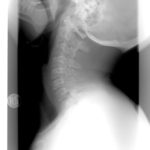

Újma na zdraví při dopravní nehodě může znamenat lehké zranění typu pohmožděnin, poranění krční páteře až těžká zranění s nutností dlouhodobé hospitalizace a vznikem trvalých zdravotních následků. Právo na odškodnění za zranění náleží tomu poškozenému újmou na zdraví, který výlučně nezavinil autonehodu. Oběť dopravní nehody se může následně obrátit s žádostí o odškodnění na pojišťovnu vozidla viníka nehody z tzv. povinného ručení.